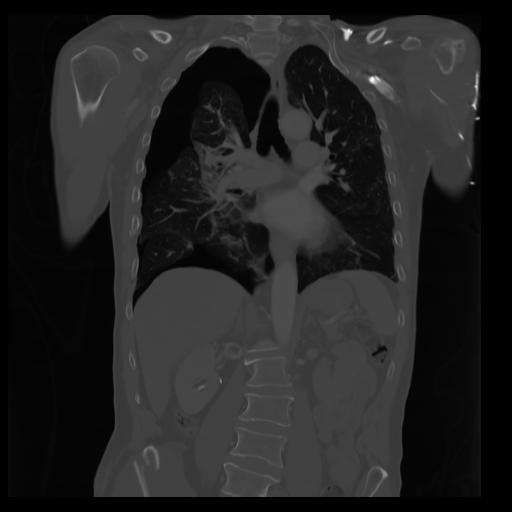

29 CUERPO,CE,Coronal,3.000,CUERPO,Coronal,